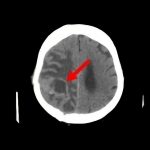

断層撮影

手術前1